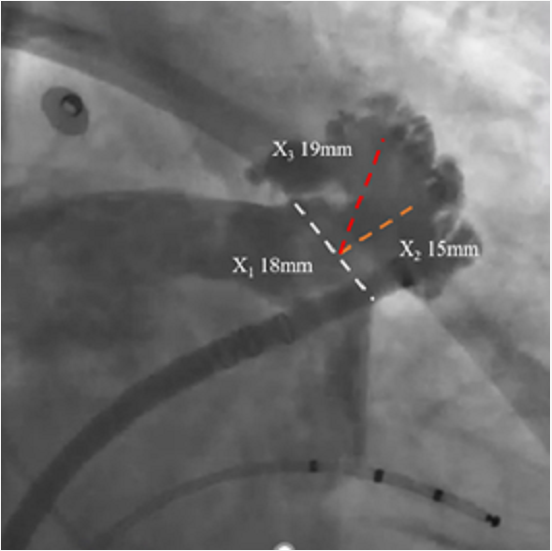

RAO30° CAU25°造影,左心耳形态充分暴露,可以观察到心耳属于反鸡翅形状。内部梳状肌较发达,深度较浅。

DSA测量开口17mm,深度19mm,与CT测量结果类似,考虑选择24mm watchman封堵器,首选X3轴向进行封堵。

术中在猪尾导管的保护下,逆时针旋转输送鞘,尽量将输送鞘送入上叶。稳定输送系统,体外预借1mm深度,送入封堵伞,逆时针旋转稳定输送鞘,术中缓慢释放封堵伞。

走上叶缓慢展开后即刻造影观察,无残余分流。压缩比测量12.5%~21%。牵拉测试稳定,符合PASS原则,可以释放。